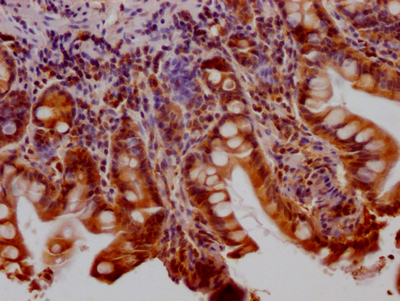

• IHC image of CSB-RA802195A0HU diluted at 1:100 and staining in paraffin-embedded human small intestine tissue performed on a Leica BondTM system. After dewaxing and hydration, antigen retrieval was mediated by high pressure in a citrate buffer (pH 6.0). Section was blocked with 10% normal goat serum 30min at RT. Then primary antibody (1% BSA) was incubated at 4℃ overnight. The primary is detected by a Goat anti-rabbit IgG polymer labeled by HRP and visualized using 0.05% DAB.

CSB-RA802195A0HU HTT重組單克隆抗體是針對亨廷頓蛋白(Huntingtin,HTT)研發的高特異性檢測工具。HTT是一種參與細胞內囊泡運輸和突觸功能的支架蛋白,其編碼基因的CAG重復異常擴展與神經退行性疾病的發病機制密切相關。本產品采用重組技術制備,具有批次穩定性和高親和力特性,經實驗驗證適用于ELISA和免疫組化(IHC)檢測,其中IHC推薦使用1:50-1:200稀釋度,能在多種組織樣本中實現目標蛋白的精確定位。驗證數據顯示該抗體在IHC應用中呈現清晰的核周及胞質特異性染色信號,背景干擾低,適用于中樞神經系統研究中的蛋白分布分析;在ELISA平臺中展現出寬泛的線性檢測范圍,可用于體外定量檢測重組HTT蛋白的表達水平。主要應用于神經退行性疾病機制研究、HTT蛋白功能探索以及相關分子通路分析等科研領域,為探究HTT在細胞內的生物學作用及病理條件下表達變化提供可靠工具。

ELISA, IHC

• 推薦稀釋比:

Application Recommended Dilution

IHC 1:50-1:200